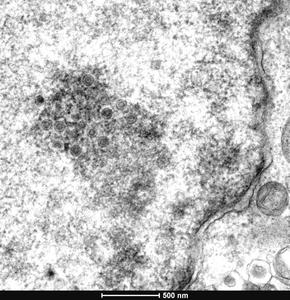

El ADN antiguo de pollos revela la mortífera evolución de un virus aviar